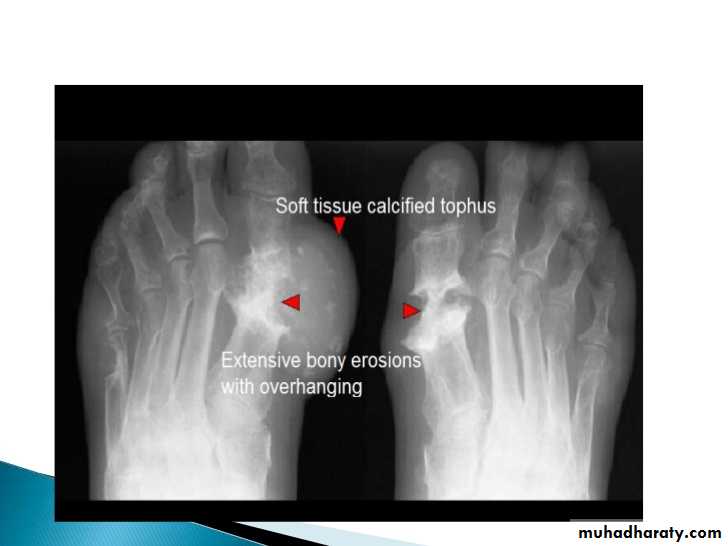

Gout

Recurrent attacks of arthritis secondary to deposition of sodium urate crystals in and around jointsHyperuricemia not always present

90% of patients are male

Radiological features are:

1.Affect lower>upper extremity, small>large joints2.First MTP is the most common site

3.Marginal paraarticular erosions; overhanging edges

4.Erosions may have sclerotic borders

5.joint space is preserved